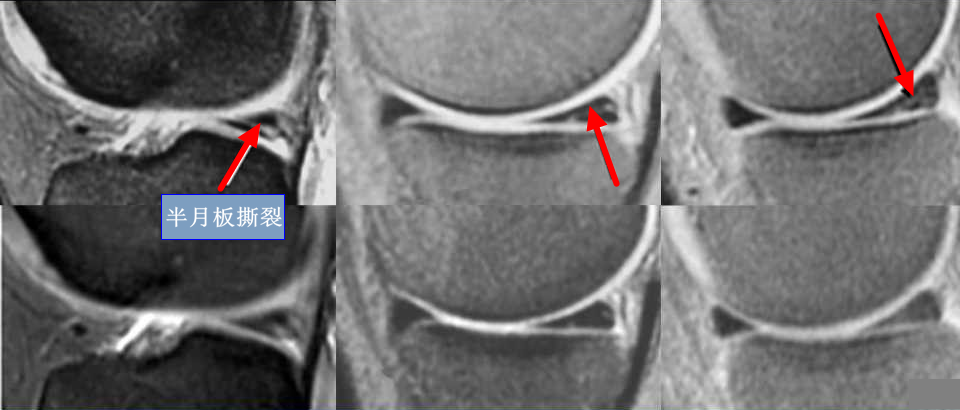

MR对病变组织的敏感度优于CT,尤其对于关节、肌肉、中枢神经系统等软组织的检查结构更清晰,是运动医学科最常用的检查的一个方法,它会观察半月板、韧带、软骨这些比较精细的软组织结构。(如下图为膝关节MR显示半月板撕裂情况)

乳腺dr能检查什么【科普】DR、CT、MR?放射科检查项目选哪个好?_https://www.jmylbn.com_新闻资讯_第5张